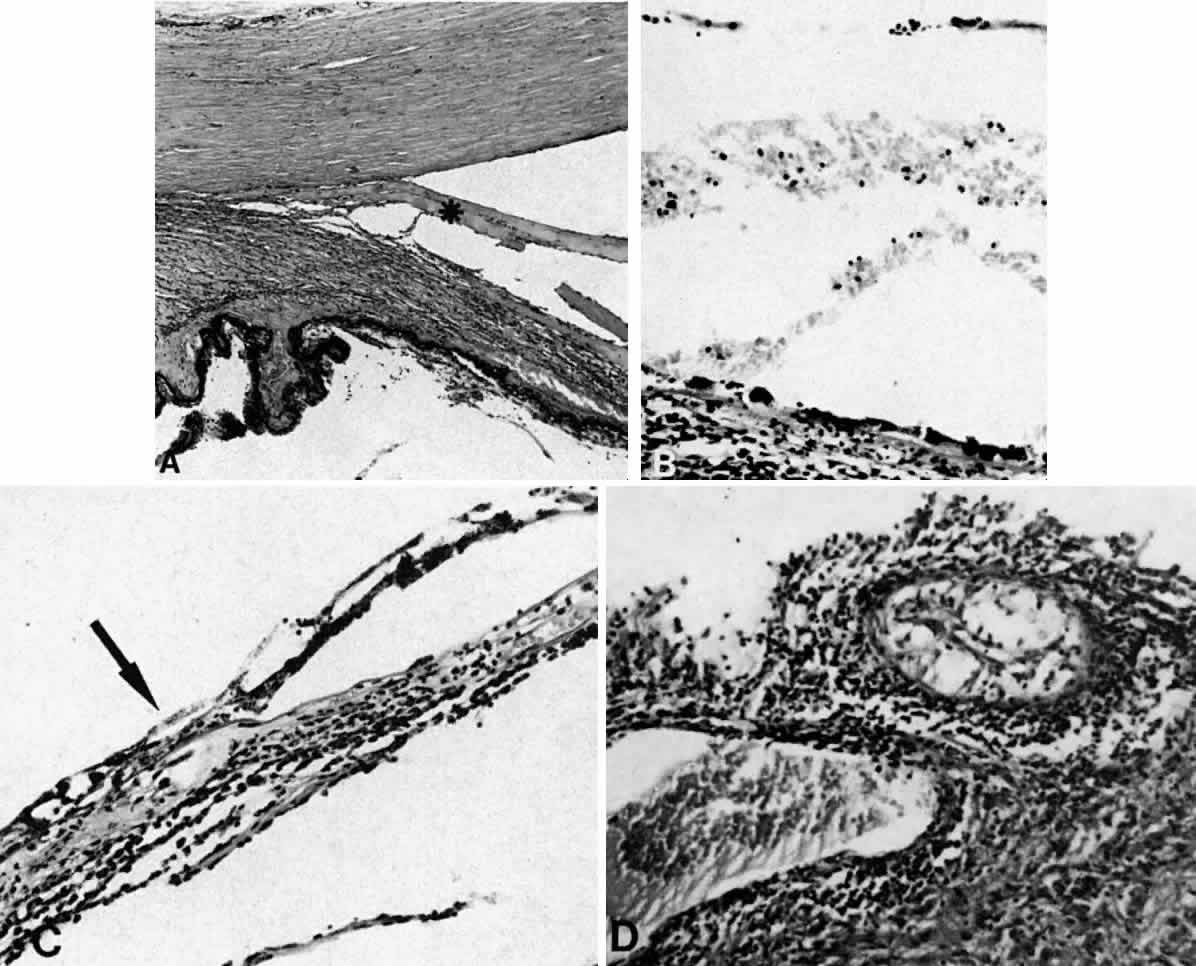

Fig. 13. A. A ciliochoroidal effusion (asterisk) associated with Toxoplasma retinochoroiditis (H & E, × 50). B. The retina temporally is totally necrotic with encysted T. gondii (H & E, × 25). C. An old chorioretinal scar (arrow) posterior to the area of necrotic retina (H & E, × 160). D. Intense vasculitis and perivascular lymphocytic infiltration of the central vessels in the optic nerve head (H & E, × 185).

Fig. 20. A 61-year-old man presented with a 10-day history of decreasing vision in the left eye.96 Examination disclosed a vision of hand motions, an irregularly shallow anterior chamber, closure of the angle, and an intraocular pressure of 45 mmHg. The ora serrata was visible without scleral depression. Ophthalmoscopic examination disclosed two large areas of solid-appearing lesions of the pars plana and anterior choroid (situated superonasally and inferotemporally), detachment of the retina, and a diffuse pigmentary disturbance, which was linear in some areas. Transscleral transillumination disclosed that areas of solid choroidal lesions lit up when viewed through the pupil. Radioactive phosphorus uptake was 16% at 1 hour, 18% at 24 hours, and 44% at 72 hours. The eye was enucleated because of the suspicion of a malignant melanoma. A. An extensive ciliochoroidal effusion (asterisks) showing mild diffuse and marked focal (arrowhead) infiltration of lymphocytes. The equatorial sclera is markedly thickened, and there is a large serous detachment of the retina (H & E, × 17). B. Edematous choroid with a large aggregate of lymphocytes (H & E, × 100). C. The equatorial area shows a thickened sclera, an edematous choroid with diffuse and marked focal aggregates of lymphocytes, localized area of retinal pigment epithelial hypertrophy and hyperplasia (arrowheads), slight folds in the retinal pigment epithelium and inner aspect of the choroid (arrows), and proteinaceous material (asterisk) in the subretinal space (H & E, × 40). D. A choroidal effusion with overlying proliferation of retinal pigment epithelium in nodular and linear configurations. Proteinaceous material is present in some areas in or beneath the retinal pigment epithelium (arrowheads) (H & E, × 180).